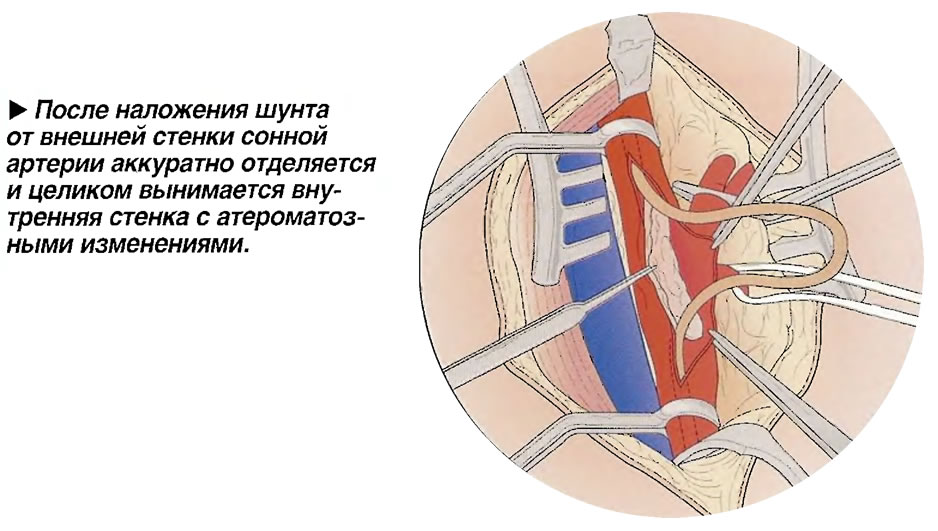

Раздел: Фотоальбом решений